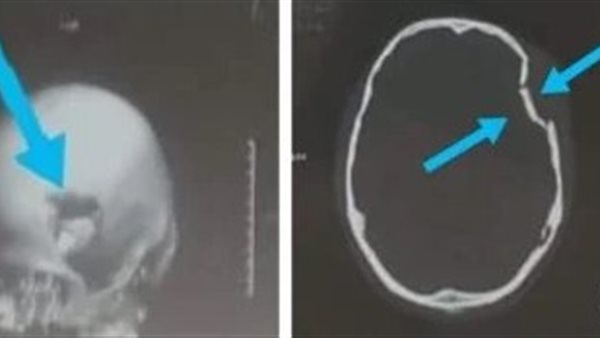

اشعة الشاب

نجح فريق جراحي بقسم جراحة المخ والأعصاب بمستشفي كفر شكر التخصصي بمحافظة القليوبية، في إنقاذ حياة شاب يبلغ من العمر حوالي 18 عاما، أصيب بكسر بالجمجمة بسبب "حجر"، أدي إلي حدوث إصابته بجرح بفروة الرأس وكسر منخسف مضاعف بعظام الجمجمة.

وأوضح الدكتور إبراهيم الغريب رئيس قسم جراحة المخ والأعصاب بالمستشفي، أنه جرى استقبال شاب يبلغ من العمر 18 عاما حضر إلي استقبال مستشفى كفر شكر التخصصي، بإصابة مباشرة بالرأس بسبب "حجر"، أدي إلي جرح بفروة الرأس وكسر منخسف مضاعف بعظام الجمجمة.

وأشار "الغريب"، إلى أنه على الفور تم مناظرة المريض عن طريق أخصائي جراحة المخ والأعصاب الموجود بالاستقبال، وتم عمل كافة الأشعة اللازمة للمريض، وتم حجز المريض بقسم جراحة المخ والأعصاب وتم استكمال التحاليل الطبية اللازمة وحجز دم للمريض، ثم تم دخول المريض العمليات لرفع الكسر وإيقاف أي نزيف، وخرج من العمليات بكامل وعيه وكامل القوة العضلية والعصبية.